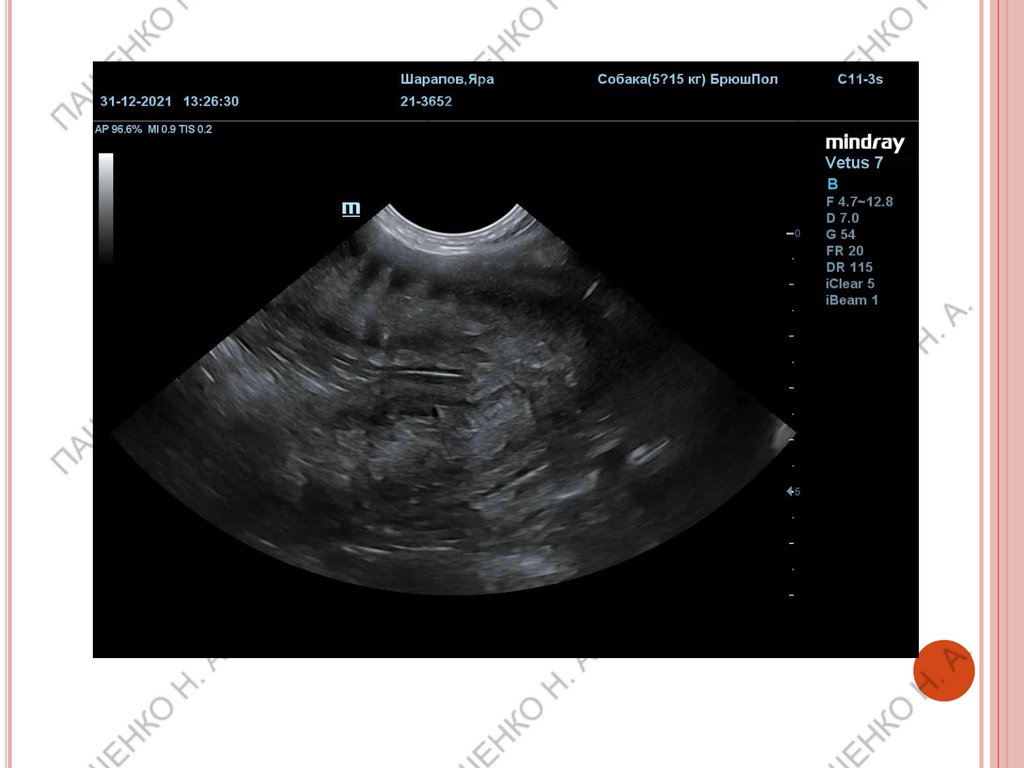

РАННИЙ СРОК (ПРИМЕРНО 22-25 ДНЕЙ)